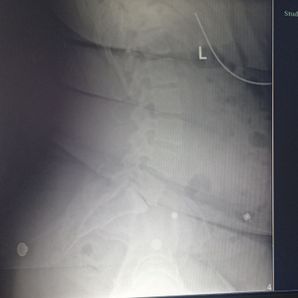

Finding out that my spine was disaligned and crooked and has spaces in my soiyne where there shouldn't be i will be out of work for a while to eliminate further damage keep me and mine in your prayers we appreciate any help